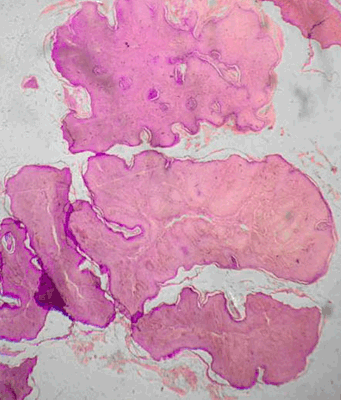

A preterm male infant was delivered by lower uterine cesarean section, with a history of polyhydramnios in the mother. The newborn infant developed repeated episodes of vomiting with regurgitation of feeds since birth. A diagnosis of congenital pyloric atresia was made for which he underwent gastroduodenostomy (Figure 1) on the fifth day of life. He also developed bullous lesions over the trunk and extremities, with new lesions developing with trivial trauma (Figure 2) (Figure 3). At six months of age, the child developed poor stream of urine with discharge of whitish flecks with fever. Urine culture was positive for Pseudomonas aeruginosa, sensitive to gentamicin. Ultrasound showed hydronephrotic changes in both kidneys with dilatation of bilateral ureters. He was diagnosed to have posterior urethral valve (Figure 4) for which vesicostomy (Figure 5) had to be done after attempts of cystoscopy guided valve fulguration were deemed ineffective in a setting of recurrent urinary tract infection and hydronephrosis. The child presented with respiratory distress and hoarseness at four and a half years of age. Thereafter, direct laryngoscopy was done which revealed multiple masses occupying bilateral false cords, left aryepiglottic fold and anterior commissure (Figure 6). The masses were firm, fleshy, pedunculated and did not bleed on touch. Biopsy was taken and surgical excision of the masses was done. The histopathology examination revealed squamous papilloma (Figure 7). The child again presented with acute severe respiratory distress with cyanosis two months following discharge, for which emergency tracheostomy had to be done. Attempts of weaning were tried but the child was unable to tolerate it. At present, the child is 9.5-year-old, tracheostomized, school-going with age-appropriate neurodevelopment. His 6.5-year-old sister underwent gastroduodenostomy for congenital pyloric atresia on 21st day of life and vesicostomy for posterior urethral valve at two years of age. She was also diagnosed with junctional epidermolysis bullosa at four years of age. The mother of the patient also suffered from polyhydramnios during the birth of her second child. There is a history of sibling death within first week of life in his father’s generation following a blistering disorder.

Figure 7: Photomicrograph showing multiple squamous papillae (H&E stain, x400).